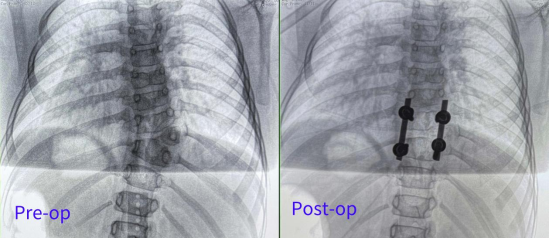

Patient: Female, 5 years old

Clinical Symptoms: Asymmetrical back, uneven shoulders, scoliosis

Surgical Indication: Congenital hemivertebra deformity accompanied by scoliosis, which affects normal growth and development. Surgical correction was necessary. Early surgical intervention can effectively prevent deformity progression and improve prognosis.

Surgical Approach: Posterior hemivertebrectomy combined with short-segment fixation and fusion

Surgical Goals: Eliminate the deforming element, correct spinal deformity, restore spinal balance, and preserve the patient's growth potential.

One-time planning for quadruple K-wire insertion

The robotic arm enhanced stabilization of surgical instruments, enabling precise execution. Guided by pre-planned trajectories, the system achieved accurate single-attempt pedicle screw placement within narrow vertebral pedicles - effectively navigating the 'anatomical labyrinth'. This approach eliminated risks associated with repeated positioning attempts. The fully integrated system demonstrated perfect coordination, successfully completing the implantation of four pedicle screws with sub-millimeter accuracy.